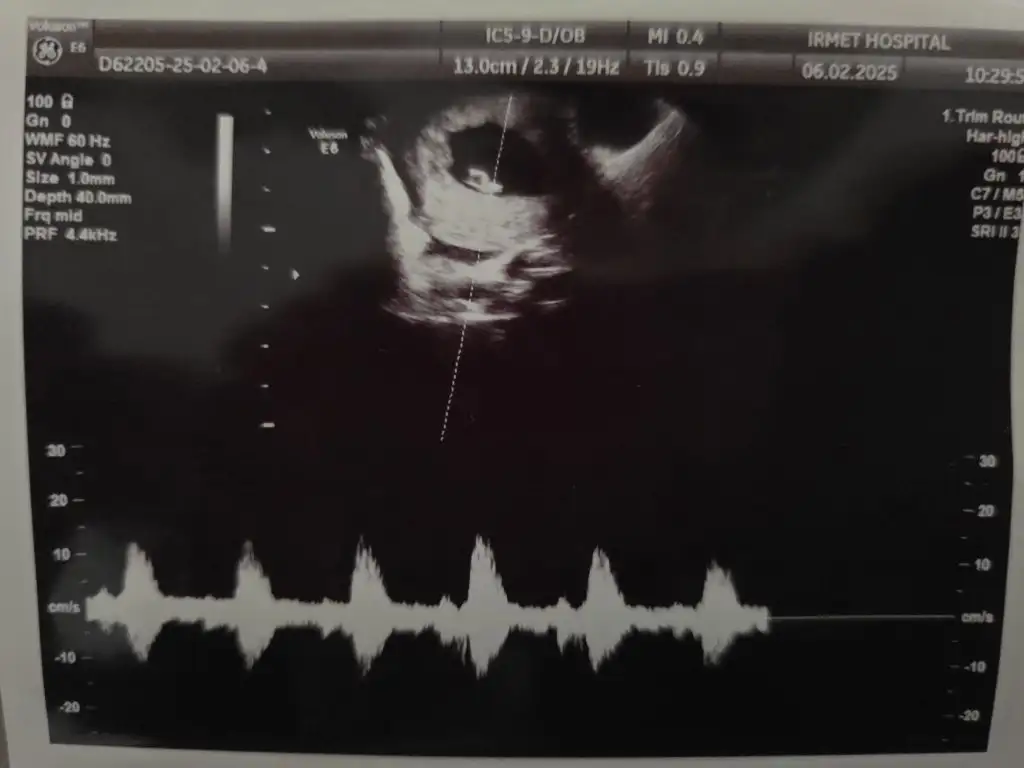

Merhaba kızlar bugün gittim karından gözükmedi

Vajinadan baktık anca öyle göründü

6+2 yim Lioo Lioo

kalp atışını da duyduk şükür 🥰 kan tahlilleri istedi rutin o kadar şuan